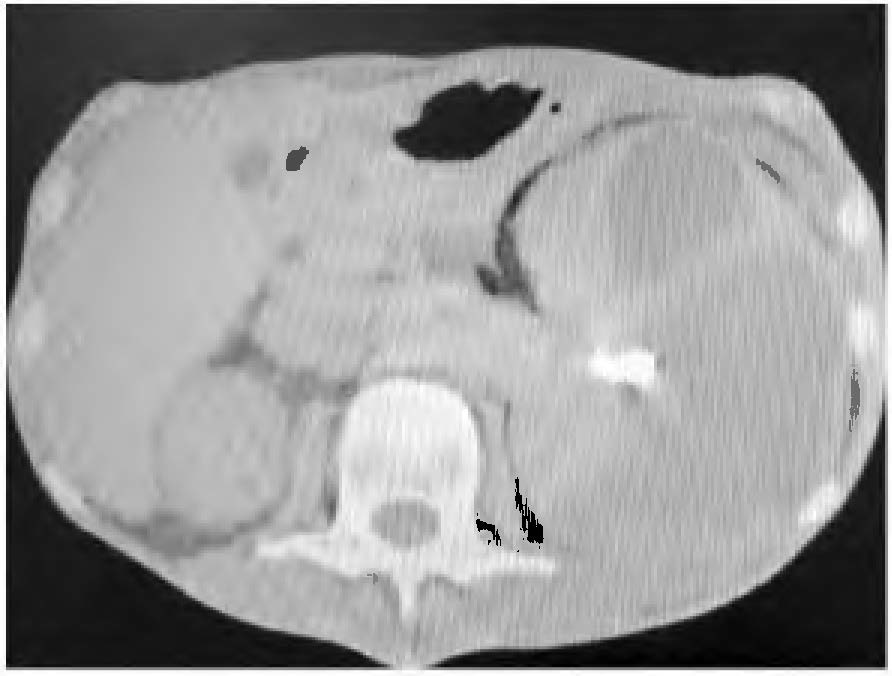

Paciente do sexo masculino, 62 anos de idade, dá entrada na emergência apresentando dor no flanco esquerdo e febre com dois meses de evolução, que se intensificaram na última semana. Realizada tomografia de abdome sem contraste, abaixo representada:

Fonte: Arquivo pessoal.

O diagnóstico que se impõe nesse caso é: